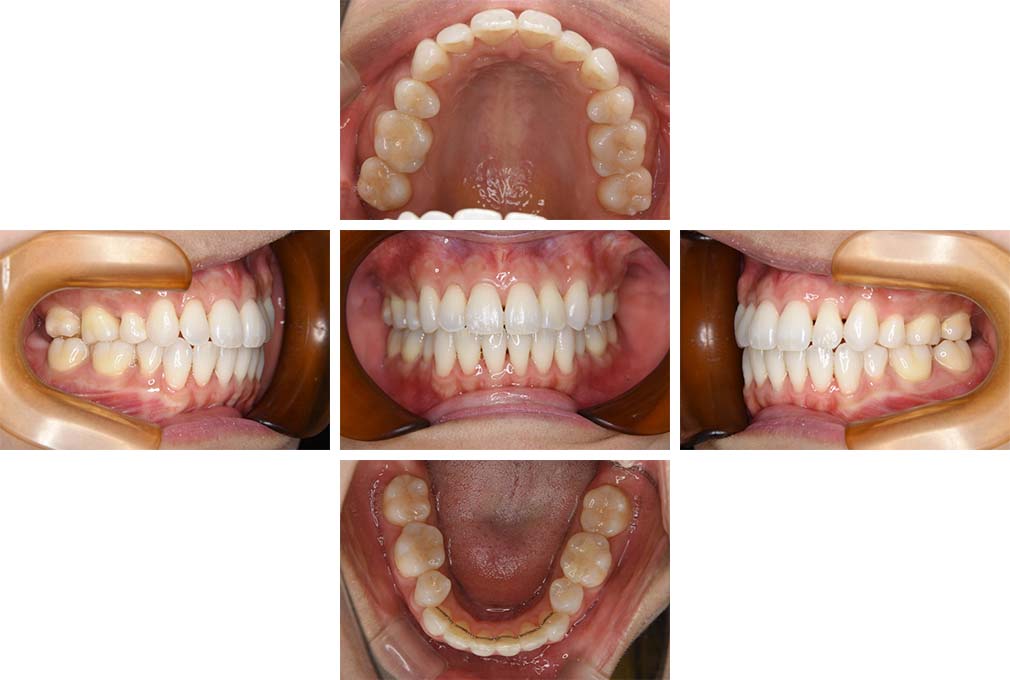

CASE:02

下顎前歯部叢生、小臼歯4歯先天欠損

初診時年齢 14歳3か月

性別 女性

治療費の目安 70万円(治療開始時)

上顎左右側小臼歯3歯、下顎左側第二小臼歯の先天欠損と下顎前歯の叢生を主訴として近隣一般歯科から紹介来院した。

上顎左側第一、第二小臼歯、右側第一小臼歯、下顎左側第二小臼歯が先天欠損であったが、左上第二乳臼歯の根の吸収がほぼ無いことから、これを残すこととして、下顎左側乳臼歯と、右側第二小臼歯を抜歯していただきマルチブラケット装置を使用して動的治療を行った。矯正用ゴムなどの協力状態も良く2年0カ月(調整来院19回)で装置を撤去し保定へ移行した。動的治療終了13年2カ月での来院時には下顎左右側智歯が萌出していたが、垂直的に萌出していたため抜歯は行っていない。

治療前

14歳3か月

治療後

動的治療期間2年0カ月

16歳7か月

13年経過

動的治療終了後13年2カ月

30歳0か月